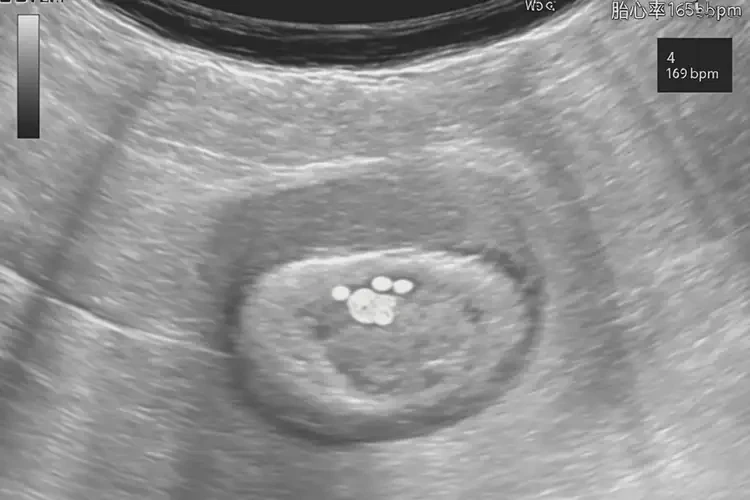

懷孕4周胎心率165怎么回事

胎心率165次/分鐘

懷孕4周時(shí),胎心率達(dá)到165次/分鐘是正?,F(xiàn)象。胎心率是指胎兒心臟每分鐘跳動(dòng)的次數(shù),通常在懷孕早期,胎心率會(huì)相對(duì)較高。以下是關(guān)于懷孕4周胎心率的詳細(xì)解釋:

1. 早期胎心率:在懷孕4-8周,胎心率通常在150-180次/分鐘之間。165次/分鐘的胎心率在這個(gè)范圍內(nèi),屬于正常情況。

懷孕4周胎心率165怎么回事(圖1)